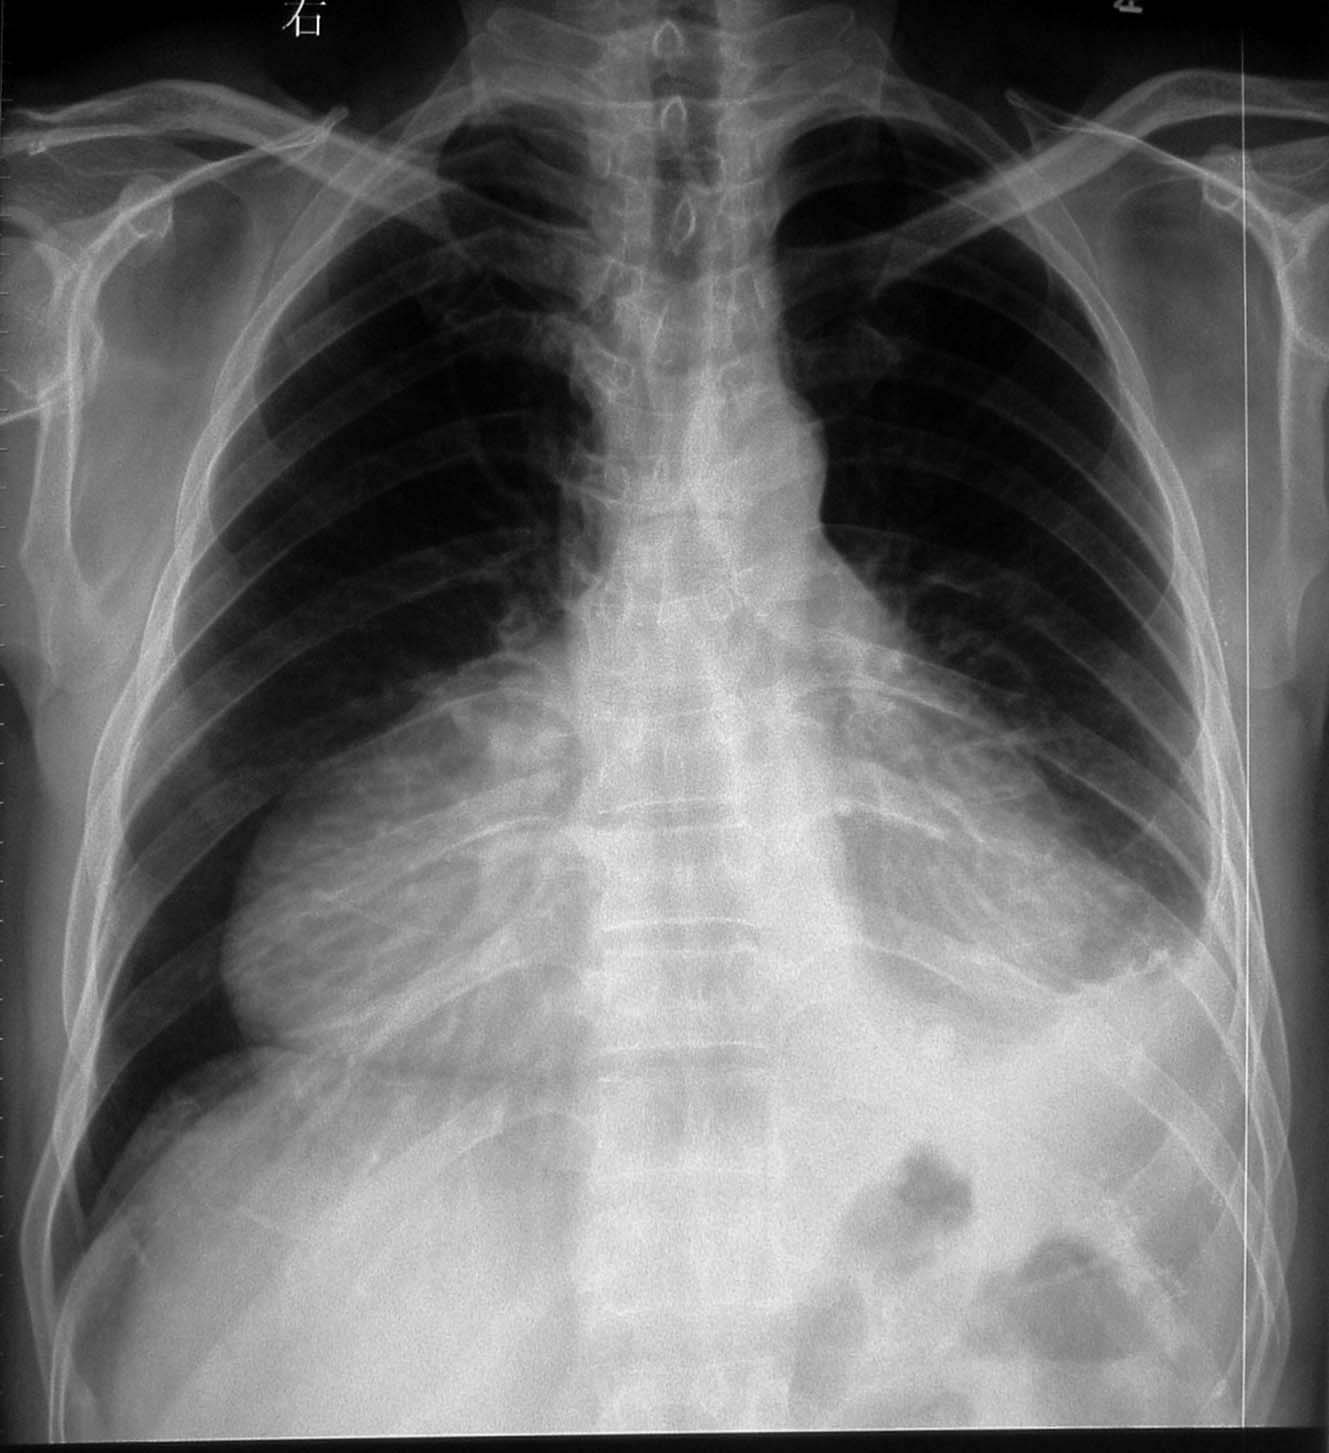

标题: CL0316:【】心包囊肿 [打印本页]

标题: CL0316:【】心包囊肿

支持心包囊肿,不过确诊还真得靠其他检查。

平片诊断是困难的 要做ct b超了

心包囊肿